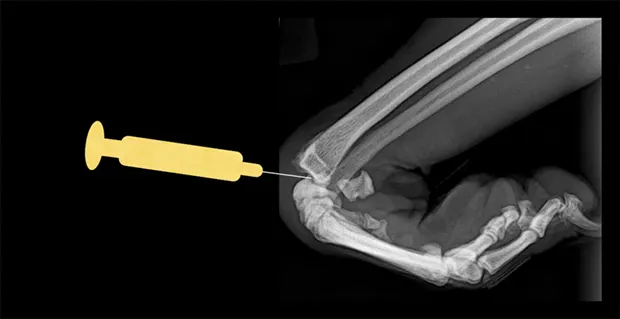

Carpus

Place the patient in lateral recumbency with the affected limb upward. The radiocarpal joint is the largest and easiest of the carpal joints to aspirate from the cranial side. Flexing the carpus by 45° opens the joint to facilitate needle entry. Palpate the cranial aspect of the distal radius, and insert the needle perpendicular to the long axis of the radius bone (parallel to the joint surface of the distal radius). Avoid penetrating the cephalic vein and tendons during the procedure by inserting the needle just medial or lateral to the midsagittal plane of the carpus.

Lateral view of carpus. Flex the carpus and insert the needle into the radiocarpal joint just distal to the distal extent of the radius bone.